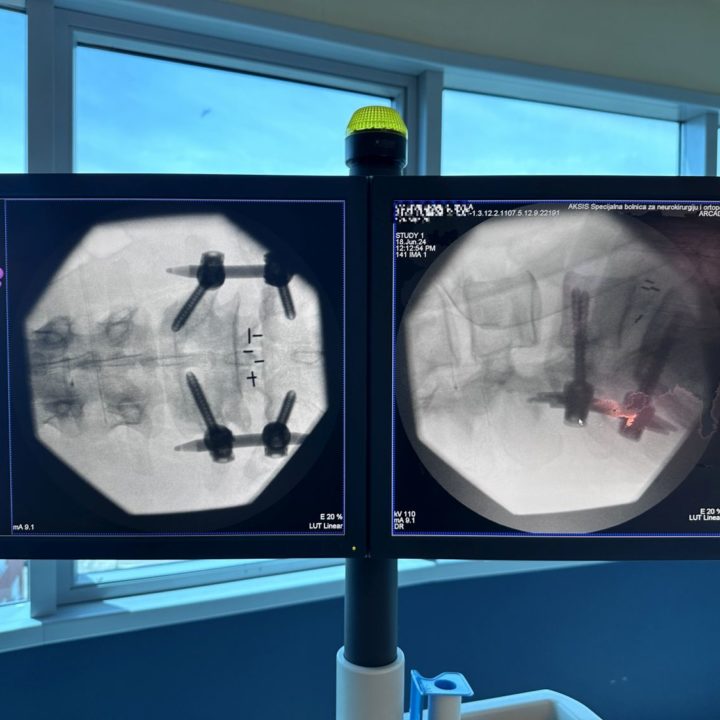

We are proud of our commitment and top results in spinal neurosurgery. In the last few days our extraordinary team performed two advanced and demanding spine surgeries that brought relief and improved quality of life to patients – METRx micro-endoscopic posterior decompression of the cervical spine, and miniOpen TLIF spinal fusion.

Our experience, knowledge and technical capabilities allow us to perform the most complex surgeries with a high success rate. Thanks to advanced technology and continuous education our neurosurgeons provide the best possible care. See the pictures below that show the precision and innovation of our procedures.